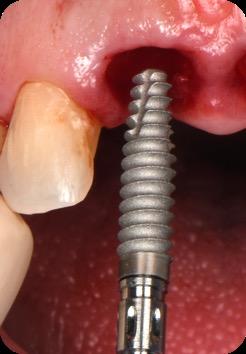

This case was performed by Dr Homa Zadeh, DDS, PhD, a respected leader in periodontology and implant dentistry. Dr Zadeh’s approach emphasizes biologically driven protocols and evidence-based techniques, making this case a strong example of clinical excellence using the Tapered Pro Conical system. It involves the replacement of two front anterior teeth after they fractured off and the full restoration process.

BioHorizons has introduced a new implant system that combines the advanced thread design of the Tapered Pro with the precision and stability of the Conelog conical connection. This integration delivers enhanced surgical handling, improved primary stability, and long-term biological benefits, supporting better patient outcomes in both aesthetic and functional zones.

Fig 5. Central incisors extracted using minimally invasive protocol. Alveolar bone and gingival tissues were intact after extraction

Fig 6. BioHorizons Tapered Pro Conical implants of 3.8 x 15mm placed according to the plan.

Fig 7. Implants immediately after installation.